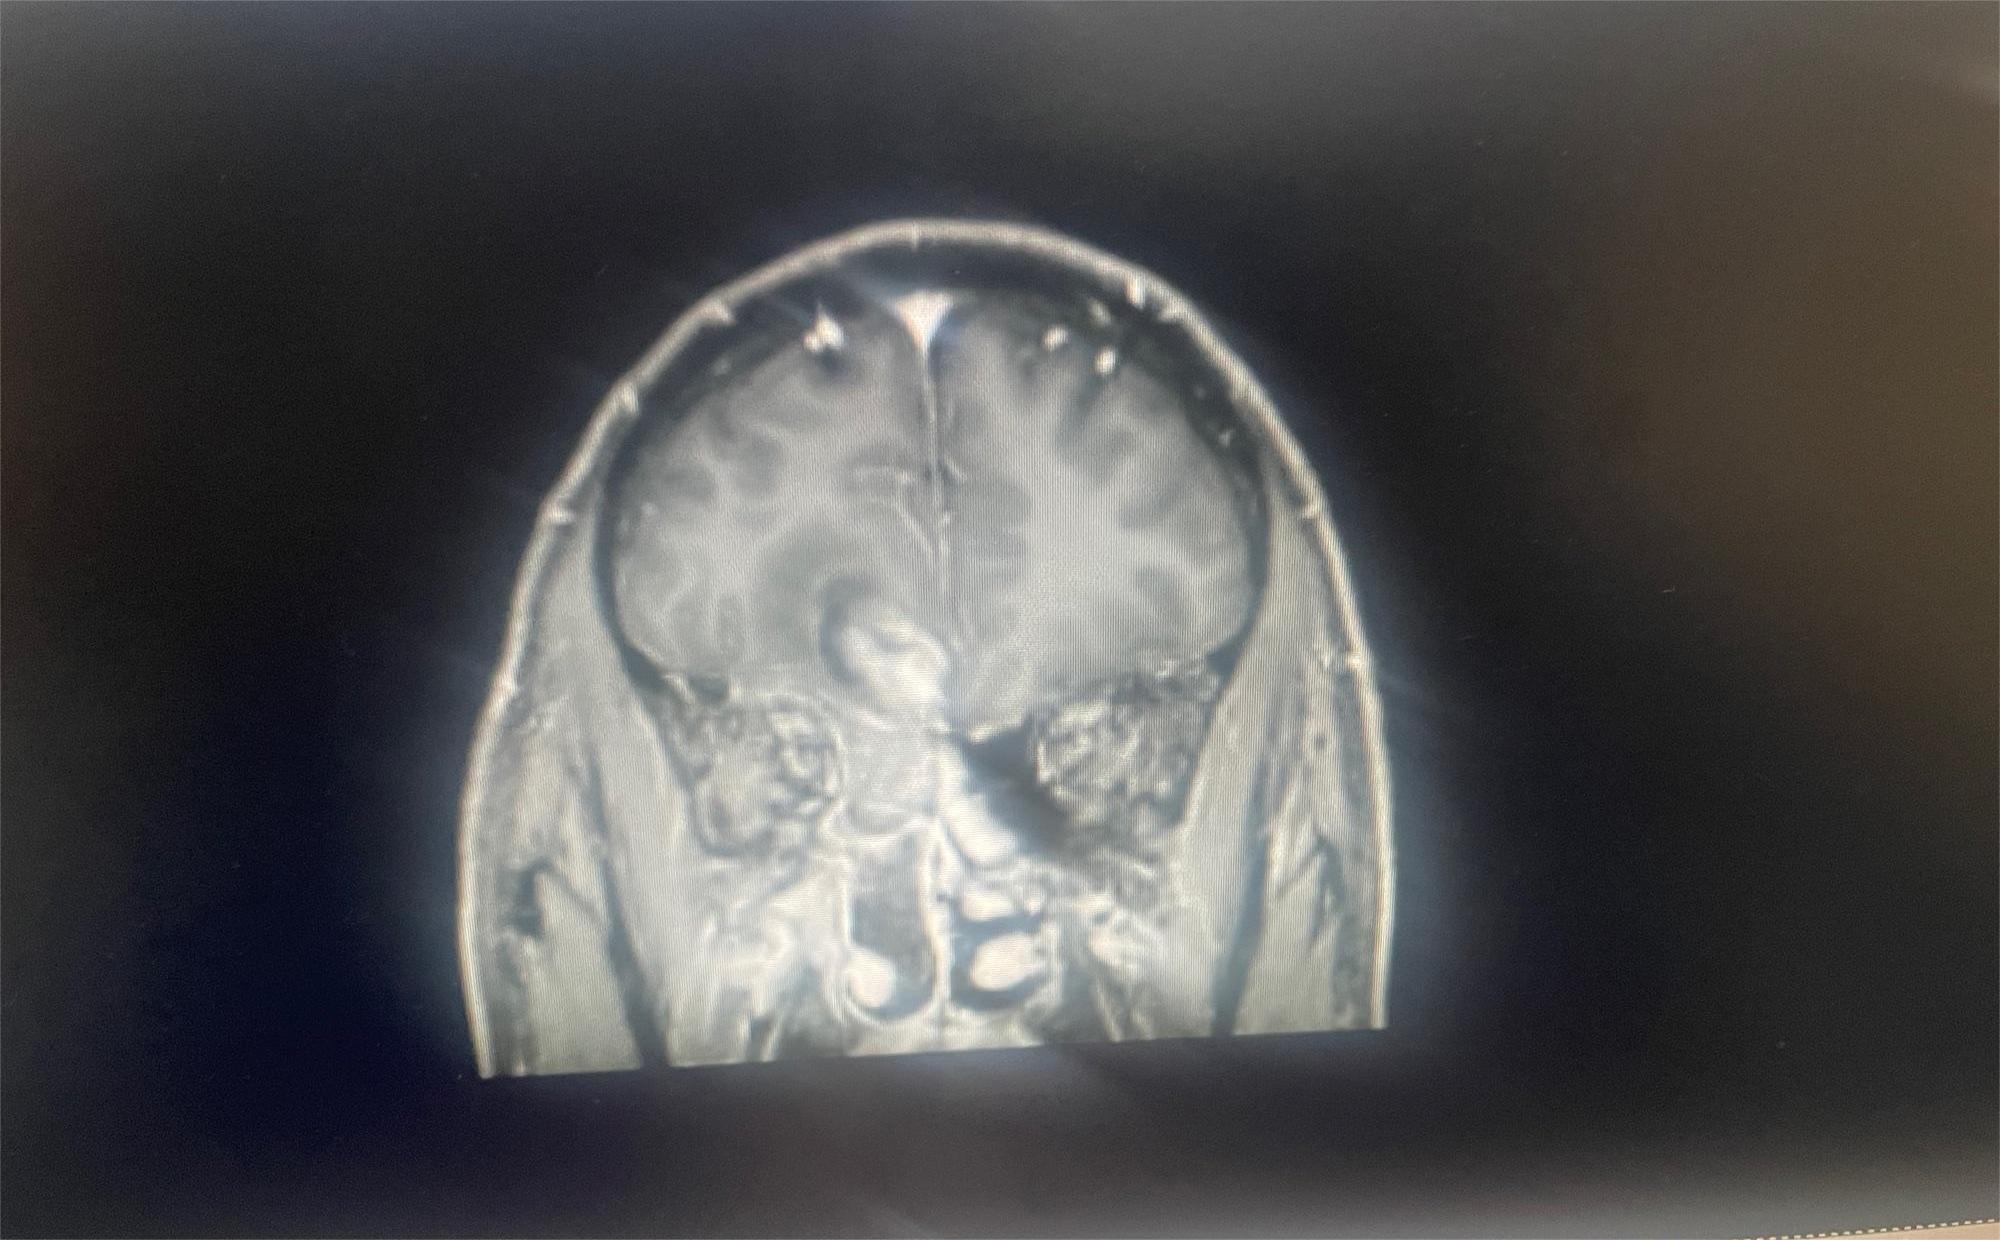

请各位帮我看下,这个情况该怎么治疗比较好,去哪里治疗,有好的医生医院介绍吗

脑部肿瘤,梗阻性积水